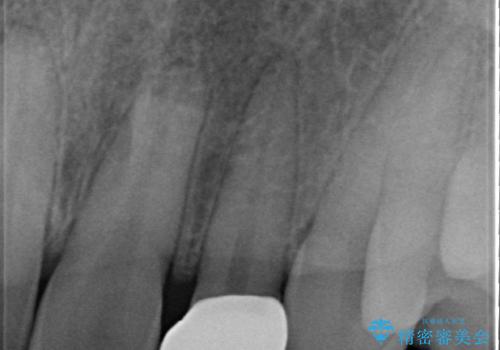

- 上顎前歯のすきっ歯が気になるといらっしゃった方の症例です。

上顎前歯のみの治療を希望されたので、部分矯正を行いました。

左上2の矮小歯はオールセラミッククラウンによる補綴を行いました。